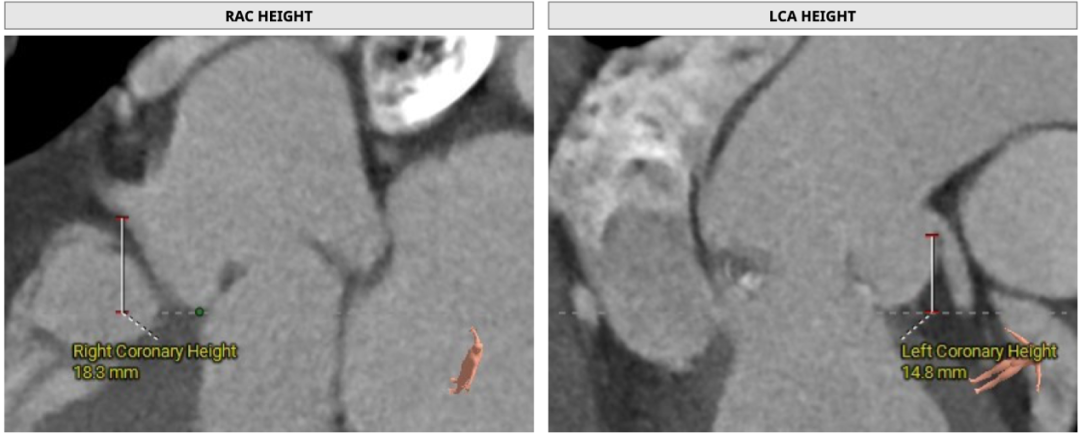

双侧冠脉开口高度可,LCA:14.8mm,RCA:18.3mm

升主动脉增宽